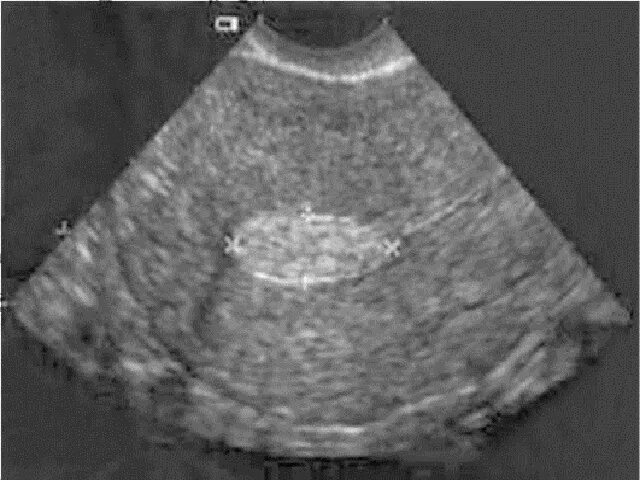

Полип эндометрия матки без операции